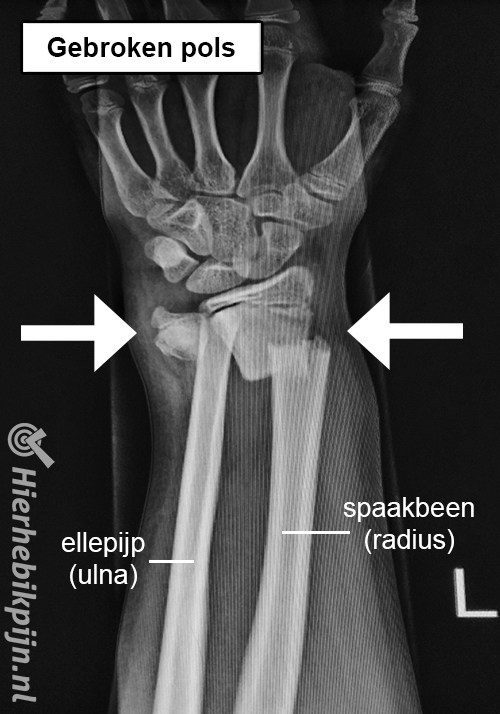

Botbreuken